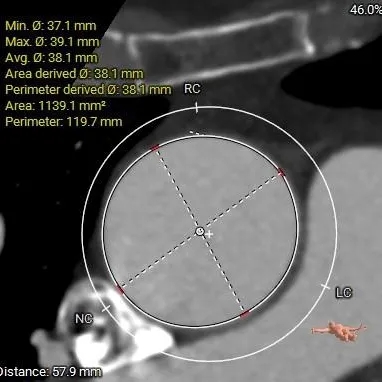

ANNULUS

周长63.6mm

周长径20.2mm

周长119.7mm

周长径38.1mm

35.6*24.7mm